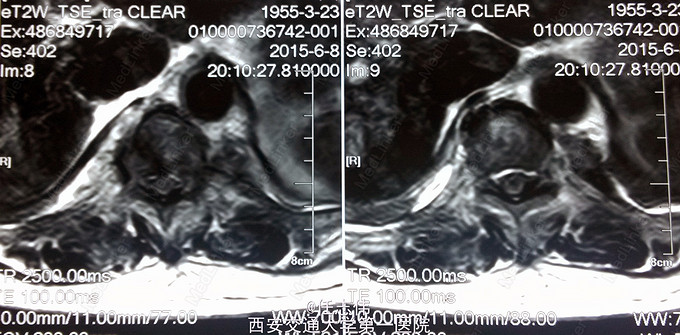

患者女性,60岁,车祸伤致双下肢感觉活动不能8h入院。 8小时前坐农用车时,被横杆撞倒腰部,摔下后感觉胸背部疼痛,双下肢活动不能,伴有短暂昏迷病史。遂来我院就诊。

左侧胸壁广泛压痛,呼吸急促。专科查体:胸背部广泛压痛,自腹股沟平面以下感觉、运动消失,腹壁反射消失,肛门反射消失,巴氏征阴性。双上肢感觉运动正常,骨盆分离挤压试验阴性。

诊断:1.胸11椎体骨折伴截瘫(Frankel A级)2.闭合性胸部损伤,肺挫伤,多发肋骨骨折,双侧胸腔积液 处理:1.急诊入院告病危,心电血氧监护;2.予以甲强龙冲击治疗;3.次日复查胸部CT,查看肺部损伤情况及胸腔积液,后予以右侧放置闭式引流。患者氧合不稳定,2日后复查胸片胸腔积液减少,予以行后路减压内固定融合术。 手术:术中见局部软组织损伤严重,胸11-12棘上、棘间韧带断裂,胸10、11、12双侧关节突有骨折移位,胸11椎板骨折,胸11左侧不能置入椎弓根螺钉,遂行单纯固定。脊髓局部挫伤明显,并有硬膜破损,予以处理。